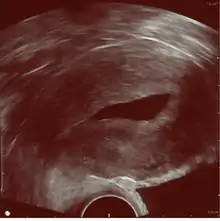

Transvaginal ultrasonography to check the location of an intrauterine device (IUD)

The examination can be performed by transabdominal ultrasonography, generally with a full bladder which acts as an acoustic window to achieve better visualization of pelvis organs, or by transvaginal ultrasonography with a specifically designed vaginal transducer. Transvaginal imaging utilizes a higher frequency imaging, which gives better resolution of the ovaries, uterus and endometrium (the fallopian tubes are generally not seen unless distended), but is limited to depth of image penetration, whereas larger lesions reaching into the abdomen are better seen transabdominally. Having a full bladder for the transabdominal portion of the exam is helpful because sound travels through fluid with less attenuation to better visualize the uterus and ovaries which lies posteriorly to the bladder. The procedure is by definition invasive when performed transvaginally. Scans are performed by health care professionals called sonographers, or gynecologists trained in ultrasound.